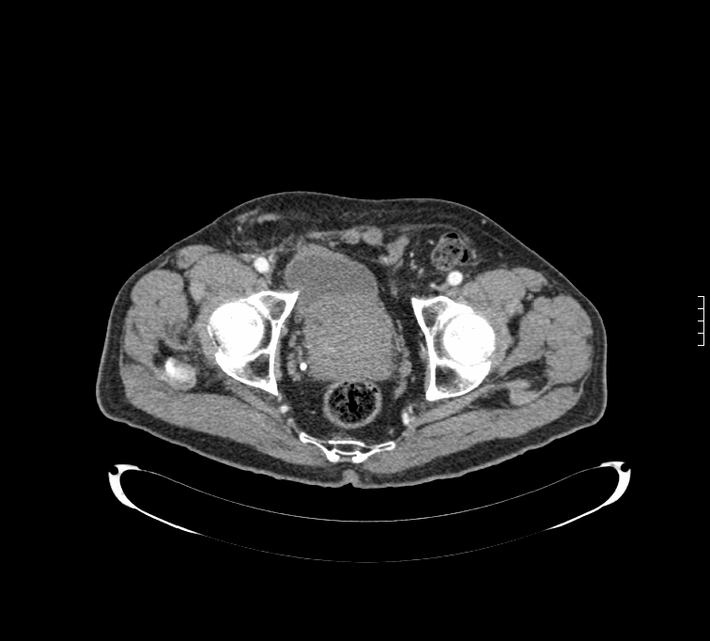

Diagnosis: Inguinalscrotal bladder herniation

Modality: CT

Credit: Submitted by Radiologist, Dr. Drazen Kovacevic M.D. to radRounds Radiology Network